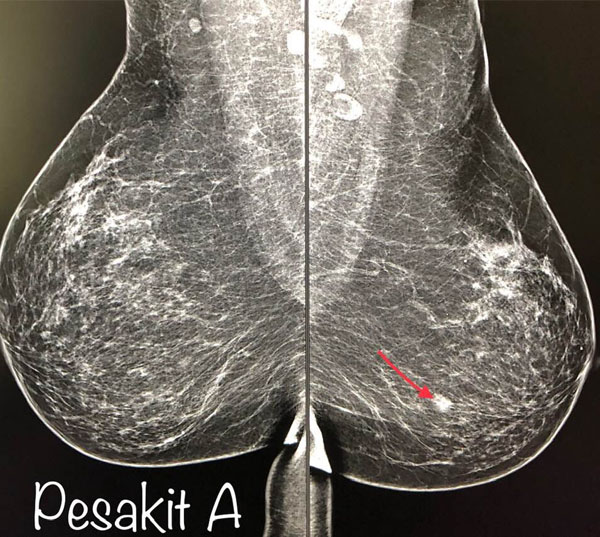

Dari segi kesan pada pemeriksaan mammogram, lihat gambar pesakit A, tak pernah ambik apa-apa suntikan, kecil saja biji kat payudara (anak panah) dah boleh nampak. Ketulan ini kurang dari 1 sentimeter, memang pemeriksaan payudara tak dapat nak rasa pun biji. Tapi mammogram boleh tunjukkan.